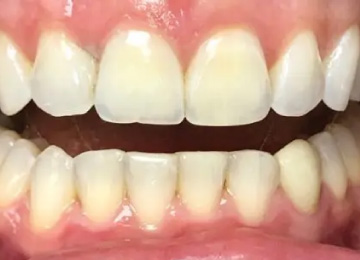

Капа для зубов: фото До и После

Фото ДО

Фото ПОСЛЕ

Наведите для просмотра

Капа для выравнивая зубов